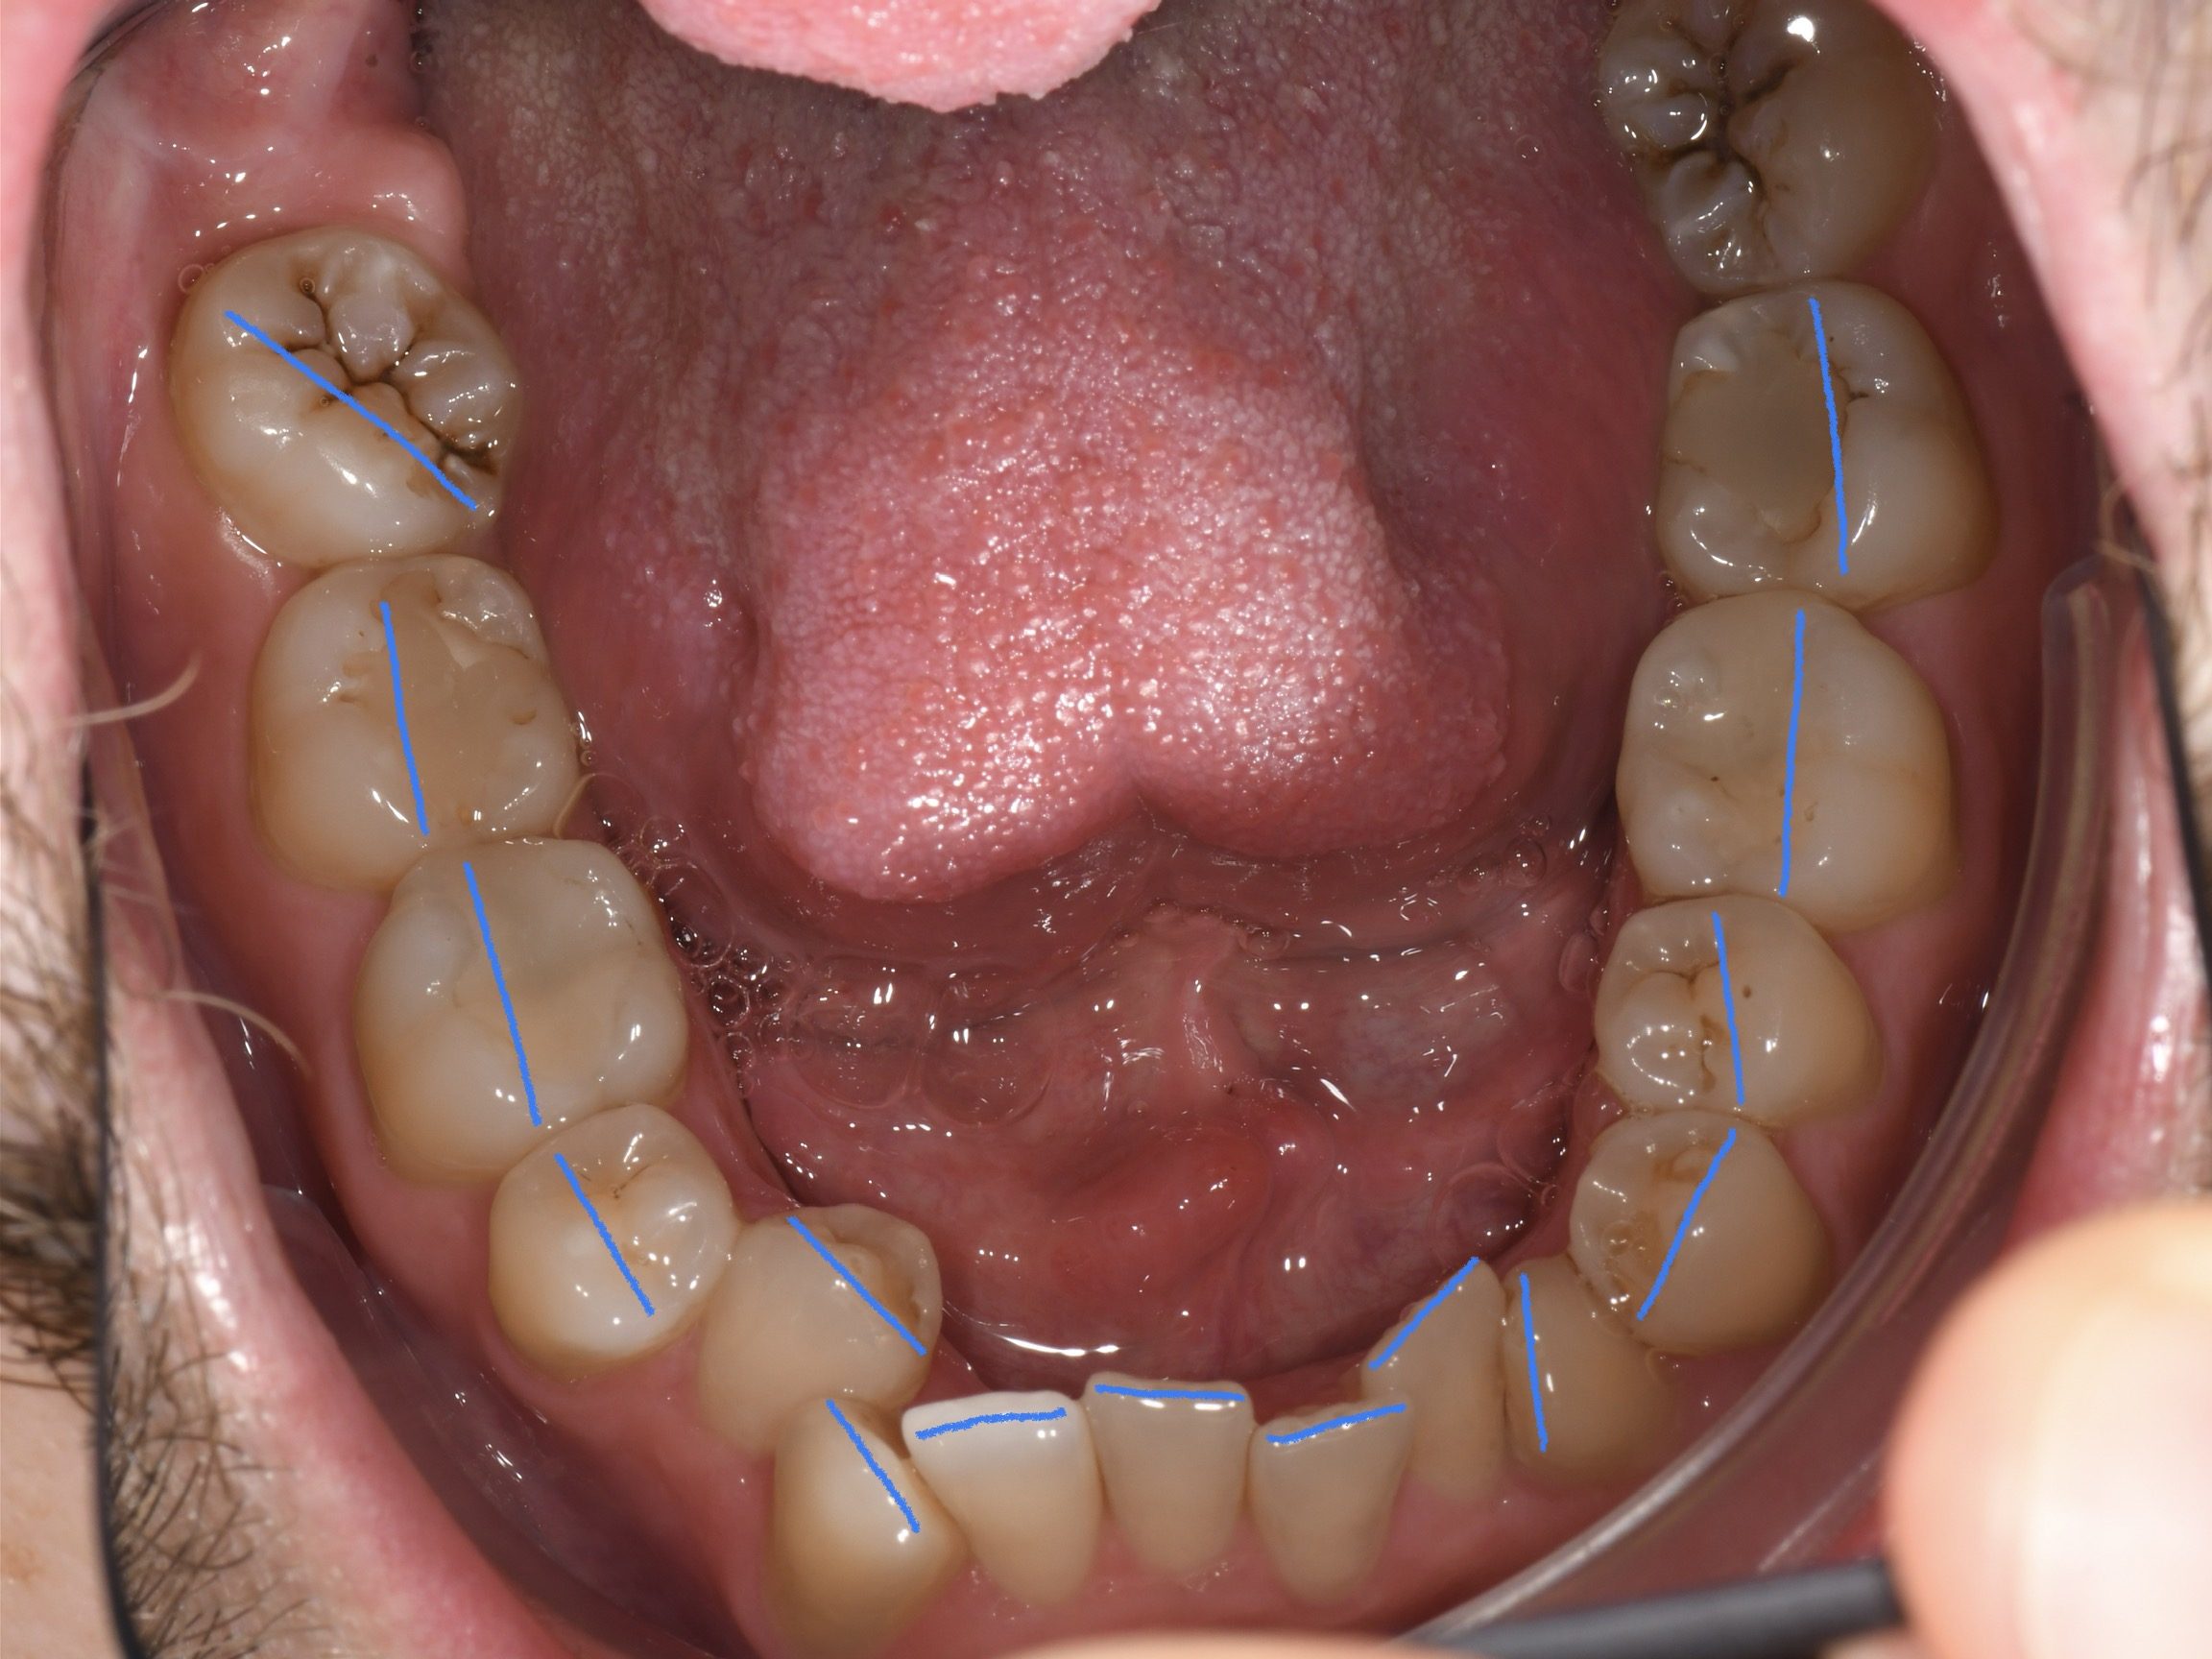

Az elmúlt évekből rengeteg szakmai referenciát tudnánk bemutatni, amelyek különböző fogszabályozási problémákat oldottak meg. Válogatva a több száz esetből, ezen az oldalon olyan képeket, információkat igyekeztünk bemutatni, amelyeknek a segítségével a jövőbeni pácienseinknek azt tudjuk üzenni: A Te fogsorod is lehet gyönyörű!

(Képeket a Pácienseink külön írásos beleegyezésével mutatjuk be!)